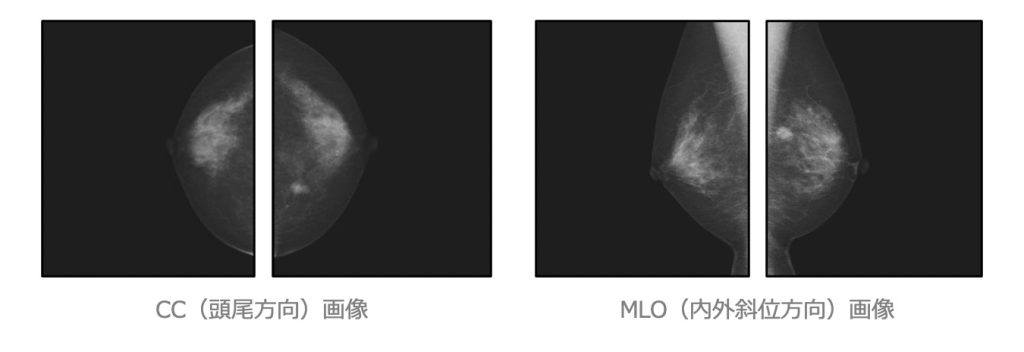

マンモグラフィ: Mammography(乳房撮影)

当院はマンモグラフィ検診精度管理中央委員会による施設認定(マンモグラフィ検診施設画像認定)を受けており、精度の高い撮影や機器管理に日々努めています。また検診マンモグラフィ撮影技術認定の診療放射線技師を中心とした女性技師が検査を担当しています。

- 軟X線(通常のX線撮影より弱いX線)を使⽤し乳房の様⼦を撮影します。

- 検査室内で専⽤検査⾐に着替えて頂きます。

- 画質向上、被ばく低減のために乳房を圧迫します。

- 圧迫時間は1回につき約20秒です。

- 撮影回数は個⼈差があります。

(必要により多⽅向撮影や拡⼤撮影を⾏います)